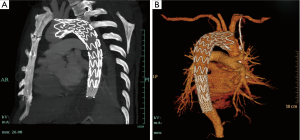

Given that the local hospital lacked cardiac surgery department, a distal bare stent restraint combined with proximal covered stent was then palliatively placed to cover the new entry tear, which kept from further retrograde dissection. After TEVAR, the patient felt symptom alleviation, but a little bit dizzy and amaurosis. CTA revealed that proximal part of stent graft covered the origins of LSCA and left common carotid (LCC) (Figure 1). He was then transferred to Zhongshan Hospital Fudan University for an open surgery on emergency. After induction of general anesthesia, the right axillary artery is exposed through a right subclavian incision as routinely used for cardiopulmonary bypass (CPB) and antegrade selective cerebral perfusion. And the femoral artery was cannulated in addition to the axillary artery cannulation. An arterial cannula is inserted into the right axillary artery, and a dual-stage caval cannula is inserted into the right atrium. The CPB flow is maintained between 2.2 and 2.4 L/min/m2, and the patient was cooled to a rectal temperature of 20 °C. During the cooling period, the ascending aorta is cross-clamped and the heart is arrested with cold blood cardioplegia. The brain is perfused through the right axillary artery at a flow rate of 5 to 10 mL/kg/min. Through the transverse incision of the ascending aorta, we found the ascending aorta dissection with a diameter of 55 mm, and confirmed that the proximal part of stent graft covered the new entry tears, as well as origins of LSCA and LCC. We cut off the dissection part of ascending aorta, aorta arch and proximal part of stent graft. A triple-branched artificial vessel was one by one sutured to the stent graft, aortic branches and ascending aorta. The CPB time was 189 minutes with aortic cross-clamp time of 117 minutes and cerebral perfusion of 30 minutes. The patient recovered well, and was discharged after 2 weeks.